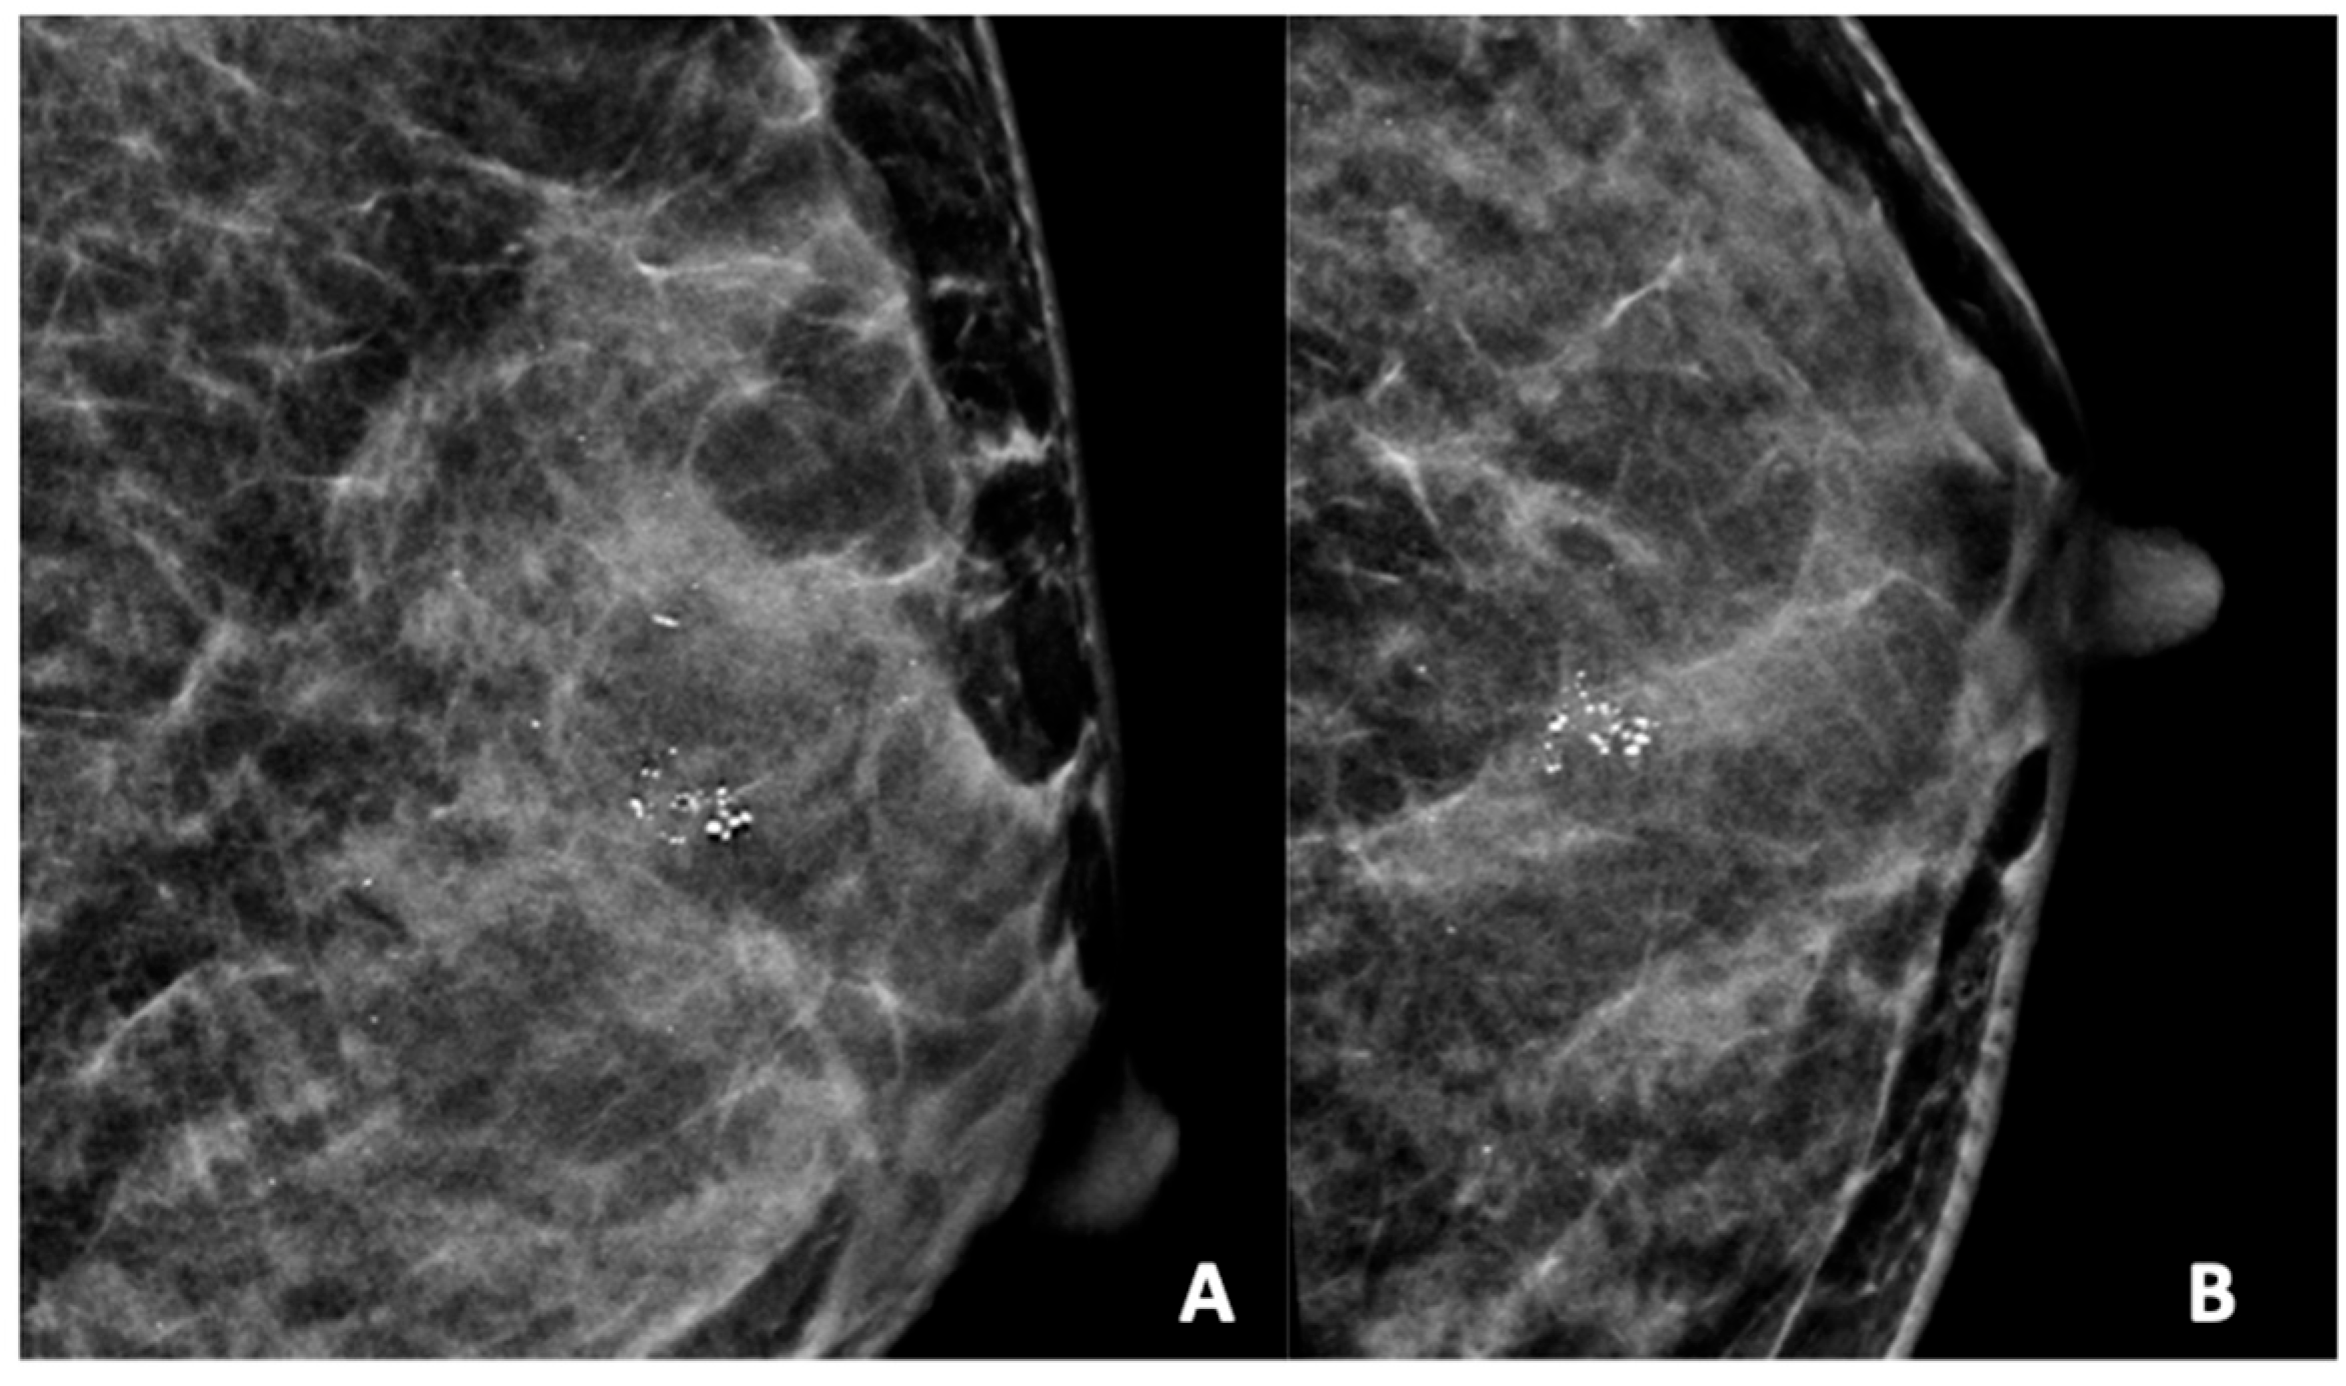

Figure 4.

Mammogram study of a left breast in (A) MLO view and (B) CC view, showing a group of heterogeneous microcalcifications in the upper mid-quadrant, reported as BI-RADS 4B. These calcifications were HPE-proven DCIS.